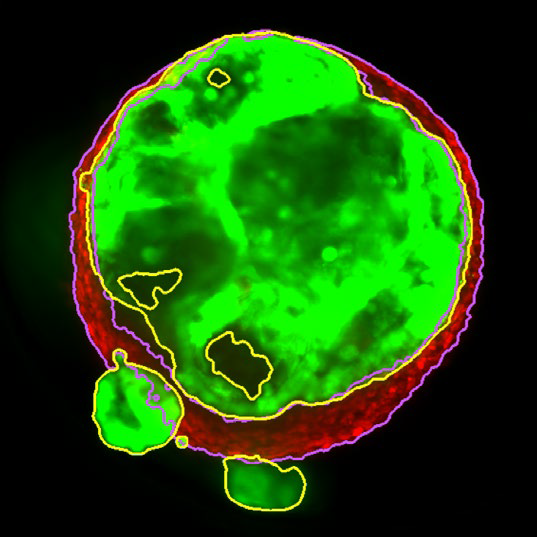

Z slice of the tumor microtissue treated with 0.05% DMSO - tumor (yellow region) and fibroblast (purple region) are recognized separately in 3D

Figure 3. Z slice of the tumor microtissue treated with 0.05 % DMSO - tumor (yellow region) and fibroblast (purple region) are recognized separately in 3D. Image Credit: Yokogawa Life Science

Z slice of the tumor microtissue treated with 5 μM Lapatinib - tumor (yellow region) is decreased significantly comparing to the one treated with 0.005% DMSO

Figure 4. Z slice of the tumor microtissue treated with 5 μM Lapatinib - tumor (yellow region) is decreased significantly compared to the one treated with 0.005 % DMSO. Image Credit: Yokogawa Life Science

Outcome

Tumor spheroids were created by seeding an Akura 384 plate with a monodispersed mixture of GFP-expressing NCI-N87 (gastric carcinoma) and RFP-expressing NIH3T3-L1 (murine fibroblast) cells, which spontaneously formed spheroids through scaffold-free self-assembly over several days. After spheroid formation, selected wells containing tumor spheroids were treated with DMSO at 0.05, 0.5, or 5.0 μM Lapatinib for six days. The images were analyzed in 3D, with NCI-N87-GFP (tumor) and NIH-RFP (fibroblast) identified separately, and the volume of each spheroid measured.